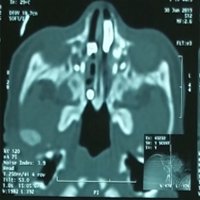

Objective: This study focuses on surgical technique, assessment of the outcomes and the recurrence rate of the disease. Patients and methods: This retrospective study was done on 18 patients with congenital choanal atresia at Azal specialized hospital and Al Kuwait University hospital, Sana’a, Yemen between 2014 and 2022. All patients underwent endoscopic repair with posterior septectomy, removal of atretic plate, lateral widening toward the pterygoid plate and creation of wide single neochoana with nasal stenting.

Results: Of 18 cases, 2 cases were excluded because of short period of follow up. Of the 16 remaining cases, 13 cases (81.25%) showed good results during the period of follow up (6 months to 9 years) from the initial surgery. Restenosis occurred in 3 (18.75%) bilateral choanal atresia cases which underwent revision surgery with good results. Conclusion: Endoscopic creation of wide single neochoana with stenting followed by close follow up and family education give good success rate.